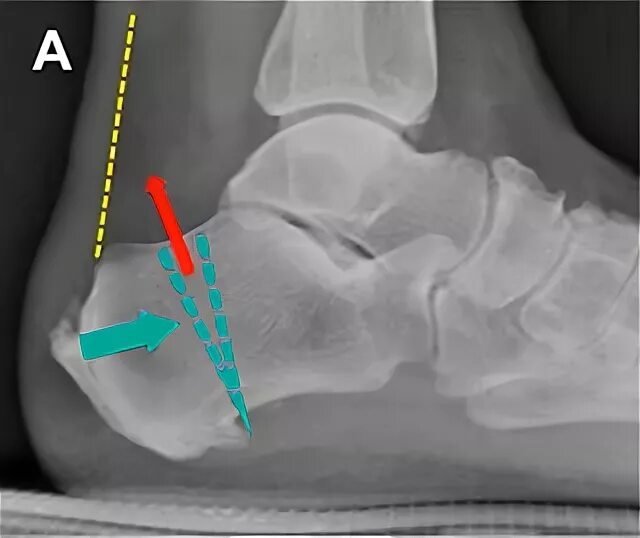

Пяточная остеотомия